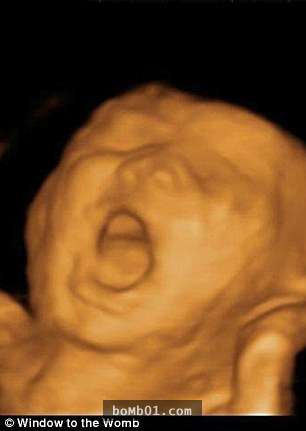

▼左邊這個寶寶看起來正在大喊,右邊這個寶寶則在思考人生。